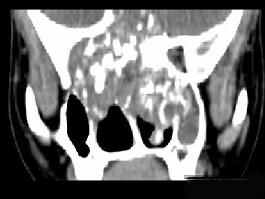

问题 男性,28岁,因鼻塞、头痛1年余,鼻窦CT扫描如图所示,请选择正确的描述与结论 ( )

选项 A、考虑鼻窦骨瘤 B、考虑为鼻窦软骨瘤 C、肿块内密度不均,有较多致密钙化影 D、窦壁及颅底骨质破坏 E、双侧上颌窦、筛窦、鼻腔及蝶窦内见软组织肿块影

答案 BCDE